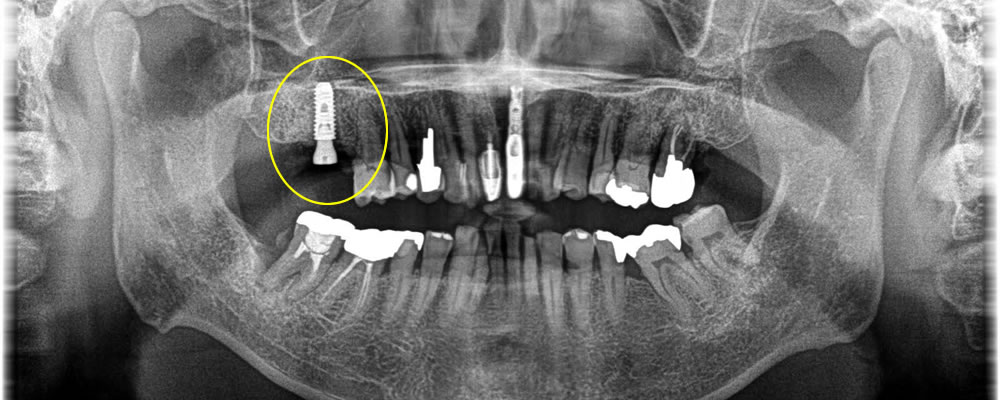

上部構造の装着・治療完了

年齢が高くなると傷の治りも遅くなってしまうので通常より少し長く4ヵ月おき、しっかりと骨とオステオインテグレーションしている事を確認し、上部に歯を作成しました。結果しっかりと噛む事ができ満足して頂く事ができました。